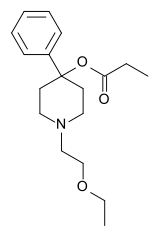

The pharmacodynamic response to an opioid depends upon the receptor to which it binds, its affinity for that receptor, and whether the opioid is an agonist or an antagonist. For example, the supraspinal analgesic properties of the opioid agonist morphine are mediated by activation of the μ1 receptor; respiratory depression and physical dependence by the μ2 receptor; and sedation and spinal analgesia by the κ receptor. Each group of opioid receptors elicits a distinct set of neurological responses, with the receptor subtypes (such as μ1 and μ2 for example) providing even more [measurably] specific responses. Unique to each opioid is its distinct binding affinity to the various classes of opioid receptors (e.g. the μ, κ, and δ opioid receptors are activated at different magnitudes according to the specific receptor binding affinities of the opioid). For example, the opiate alkaloid morphine exhibits high-affinity binding to the μ-opioid receptor, while ketazocine exhibits high affinity to ĸ receptors. It is this combinatorial mechanism that allows for such a wide class of opioids and molecular designs to exist, each with its own unique effect profile. Their individual molecular structure is also responsible for their different duration of action, whereby metabolic breakdown (such as N-dealkylation) is responsible for opioid metabolism.

Phenylpiperidines

- Pethidine (meperidine)

- Ketobemidone

- MPPP

- Allylprodine

- Prodine

- PEPAP

- Promedol